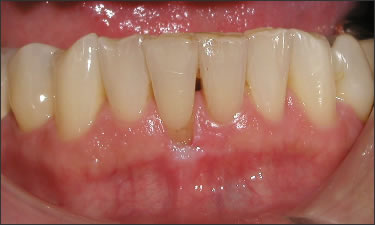

This patient experienced many areas of gum recession, primarily on the upper and lower front teeth. This patient's own tissue was used to correct the problem.